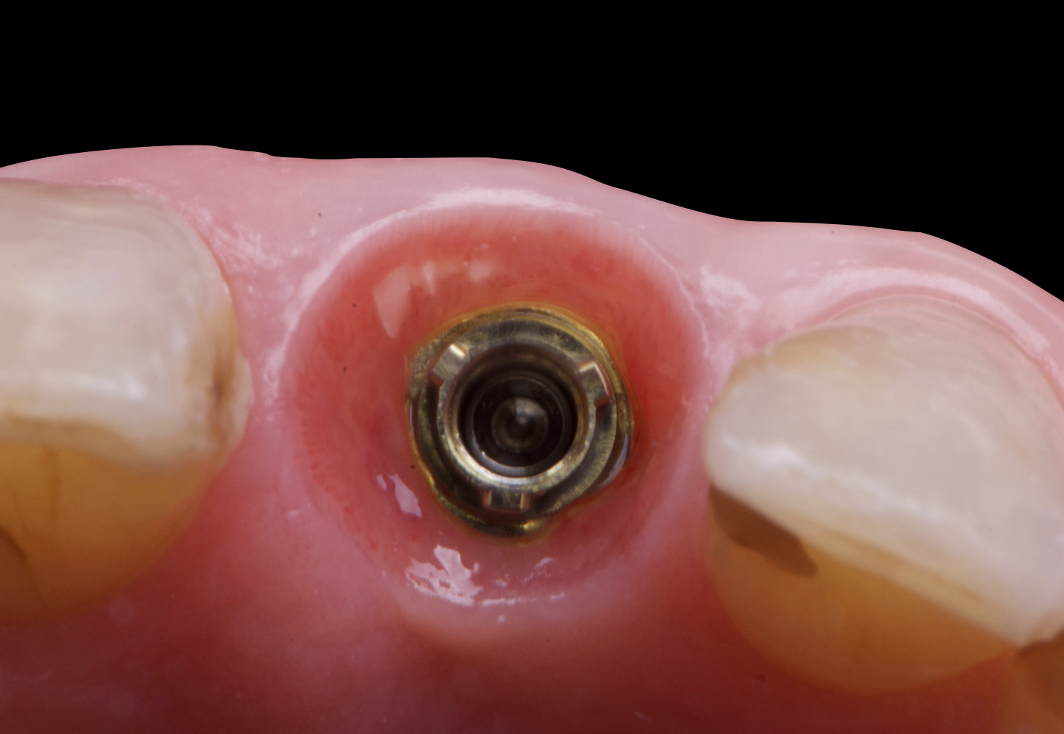

The surgical protocol began with the atraumatic extraction of tooth 1.1 to preserve as much of the alveolar socket as possible. Immediately following extraction, an N1 implant was placed into the socket using a guided surgical approach to ensure ideal three-dimensional positioning. The “one abutment one time” technique was applied to minimize soft tissue manipulation during the healing phase, which is particularly important in esthetic areas.

On the same day as the surgery, an immediate-load provisional crown was delivered. This restoration was fabricated in acrylic resin and screw-retained on the implant, following the “one abutment one time” principle. The provisional crown was carefully adjusted to avoid occlusal loading while supporting the peri-implant soft tissue architecture during the healing phase.